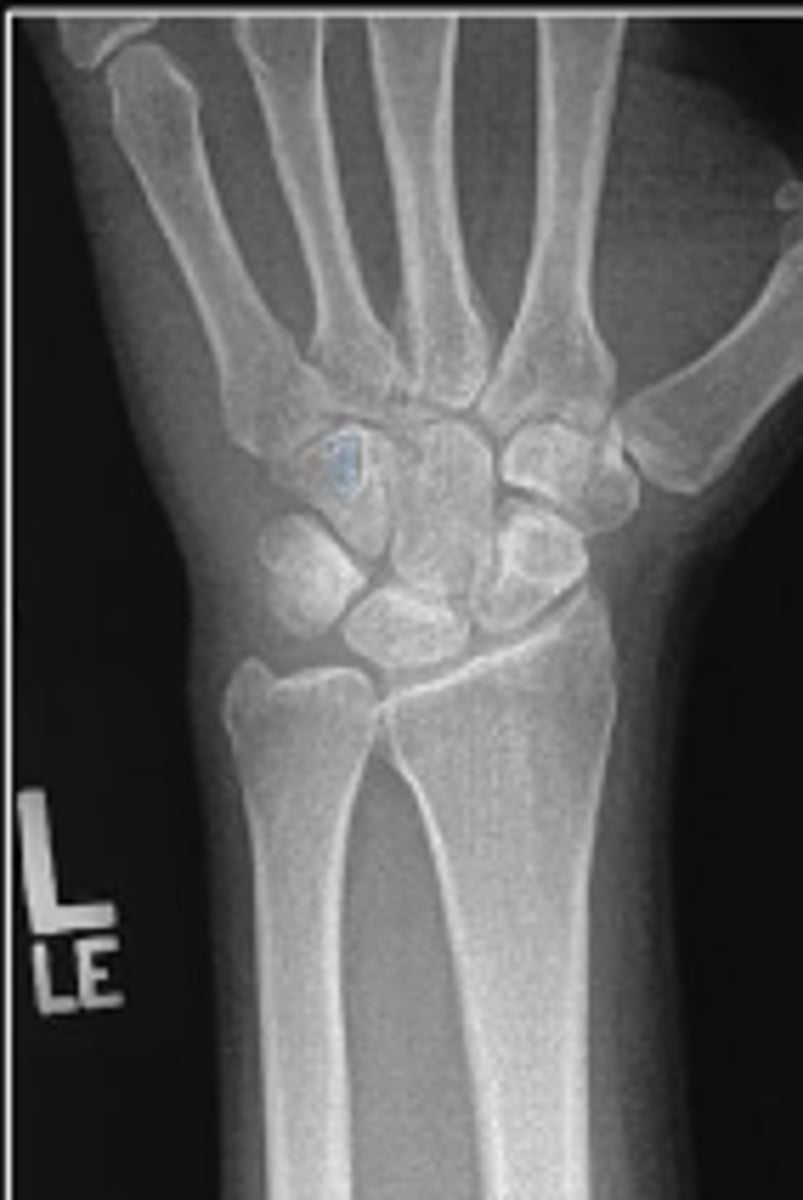

PA of the left wrist

What is the name of the radiographic view?

Left scaphoid

What is outlined?